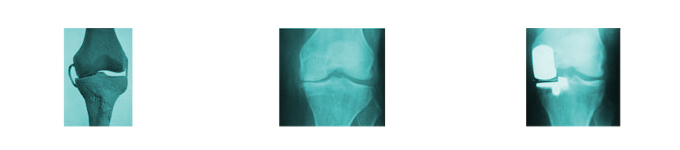

SCORE 5

60%

Medial Wear Bone on Bone Lateral Subluxation (Deficient ACL)